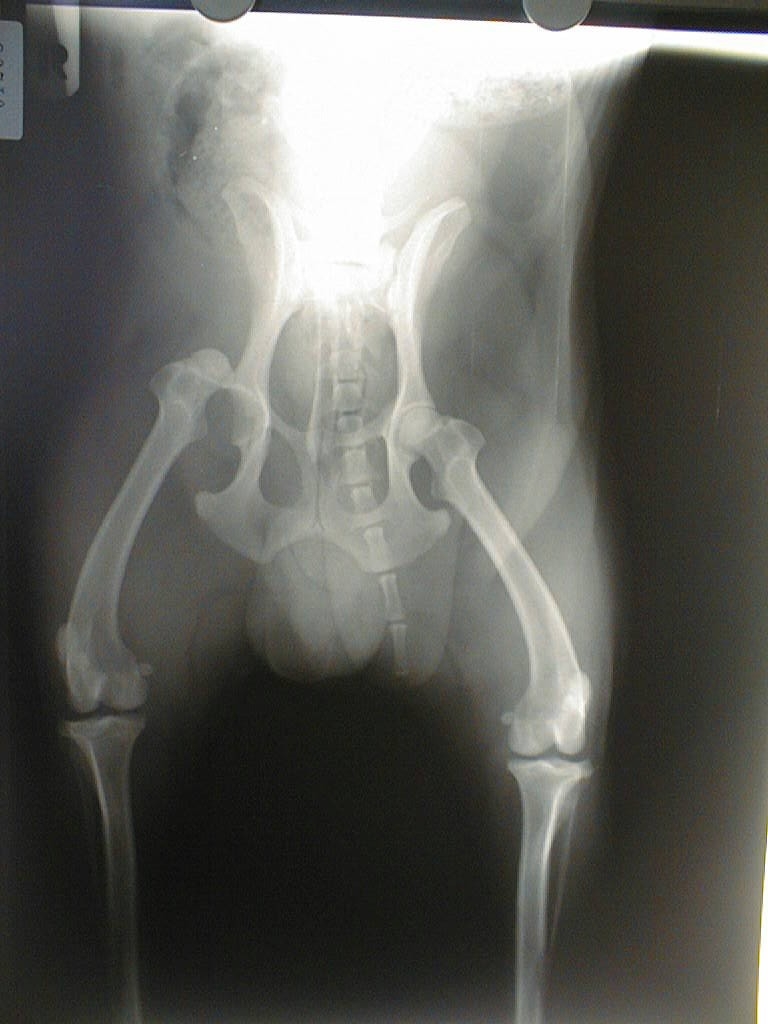

Hüftgelenksluxation

Bohrdraht-Fixation

Toggle Pin - Anker - Fixation